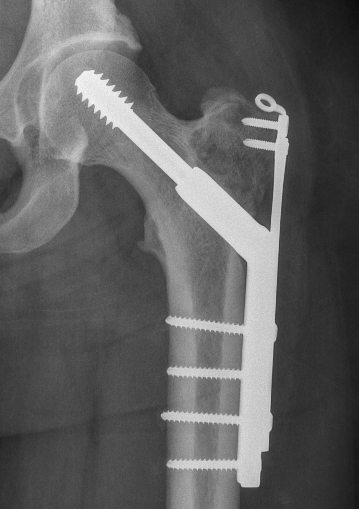

Intra - Lesional Curettage + Bone Graft

Cementing Bone graft and cement

Technique

- cortical window

- care with growth plate

- meticulous debridement with burr

- fill defect with bone graft / cement

- stabilize if necessary

Wide Resection / Allograft / Prosthesis

Indication

- articular surface compromised

- joint collapse

- recurrence after previous surgery